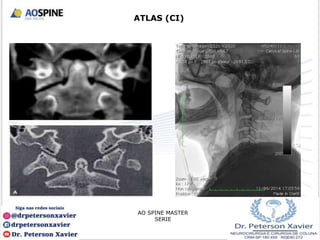

ATLAS (CI)

• Não tem corpo nem processo espinhoso;